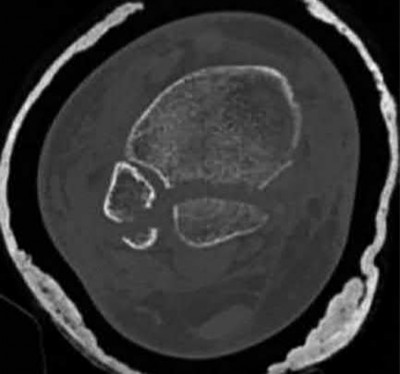

Question 3:

A 15-year-old boy presents with a permeative lytic lesion in the femoral diaphysis with aggressive periosteal reaction ('onion skinning'). Biopsy reveals uniform small round blue cells. Cytogenetic analysis of this tumor will most likely demonstrate which of the following translocations?

Correct Answer: t(11;22)

Explanation:

The clinical and radiographic description is classic for Ewing sarcoma. The characteristic cytogenetic abnormality is a balanced translocation t(11;22)(q24;q12), which fuses the EWS gene on chromosome 22 with the FLI1 gene on chromosome 11. This is seen in approximately 85-90% of Ewing sarcomas. t(9;22) is the Philadelphia chromosome (CML), t(X;18) is seen in synovial sarcoma, t(2;13) in alveolar rhabdomyosarcoma, and t(12;16) in myxoid liposarcoma.